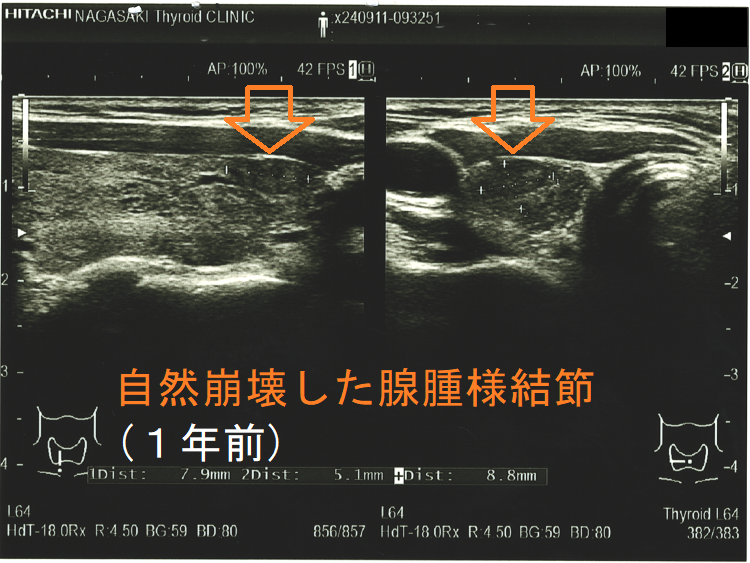

穿刺細胞診後内部融解

ケース①

ケース②